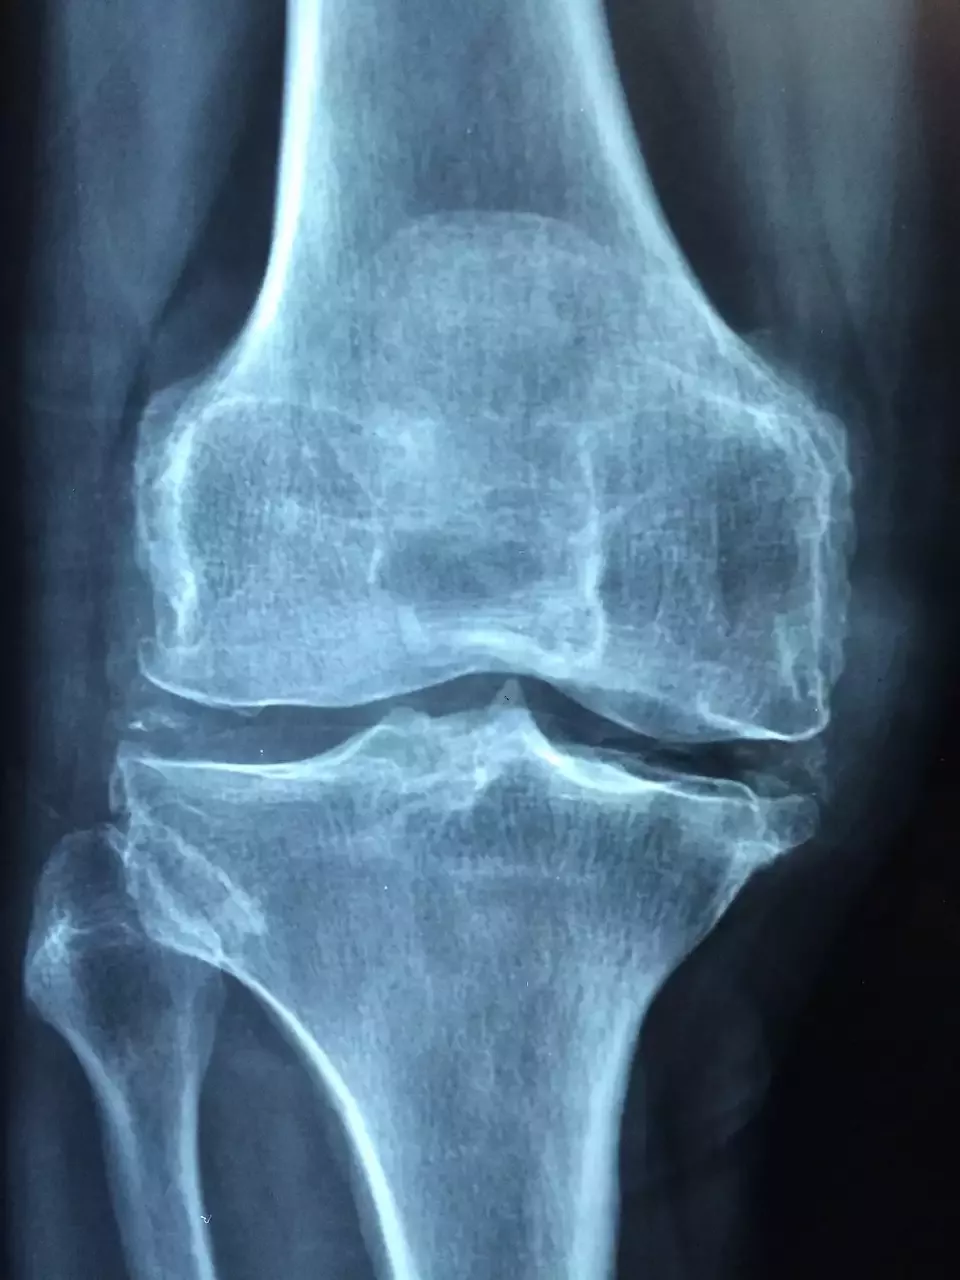

דאגות בריאות האישה ואוסטאופורוזיס